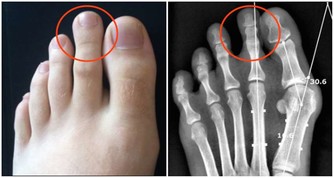

9.會引起頸椎僵硬: 久坐會影響頸動脈對頭部的供血,還破壞了正常生理彎曲,容易出現弓背或骨質增生。

10.易發生肌肉痙攣: 久坐使血流不暢,肌肉僵硬、痠痛、萎縮,使肌肉失去力量和彈性而發生痙攣。 11.會引起腰背疼痛: 久坐使得整個軀體重量全部壓在腰骶部,使腰背肌長期處於緊張狀態。